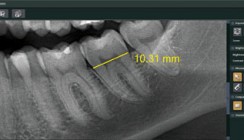

Ob Panoramaaufnahme oder 3D-Volumen - die Bildqualität des Veraview X800 ist brillant und bietet auch in den anspruchsvollsten Fällen die Sicherheit, eine präzise Diagnose zu stellen und den bestmöglichen Behandlungsweg zu wählen. Dabei ist das Gerät besonders einfach und sicher zu bedienen. Mit einer absoluten Bildschärfe dank einer Voxelgröße von 80 µm und einer maximalen Auflösung von mehr als 2,5 LP/mm sowie innovativen Funktionen zur Artefakt-Reduktion und Bildoptimierung auf Grundlage von Echtzeitdaten bringt das Kombinationsgerät jedes Detail ans Licht. Damit ist Veraview X800 die beste Basis für das Vertrauen der Patienten und den Behandlungserfolg.